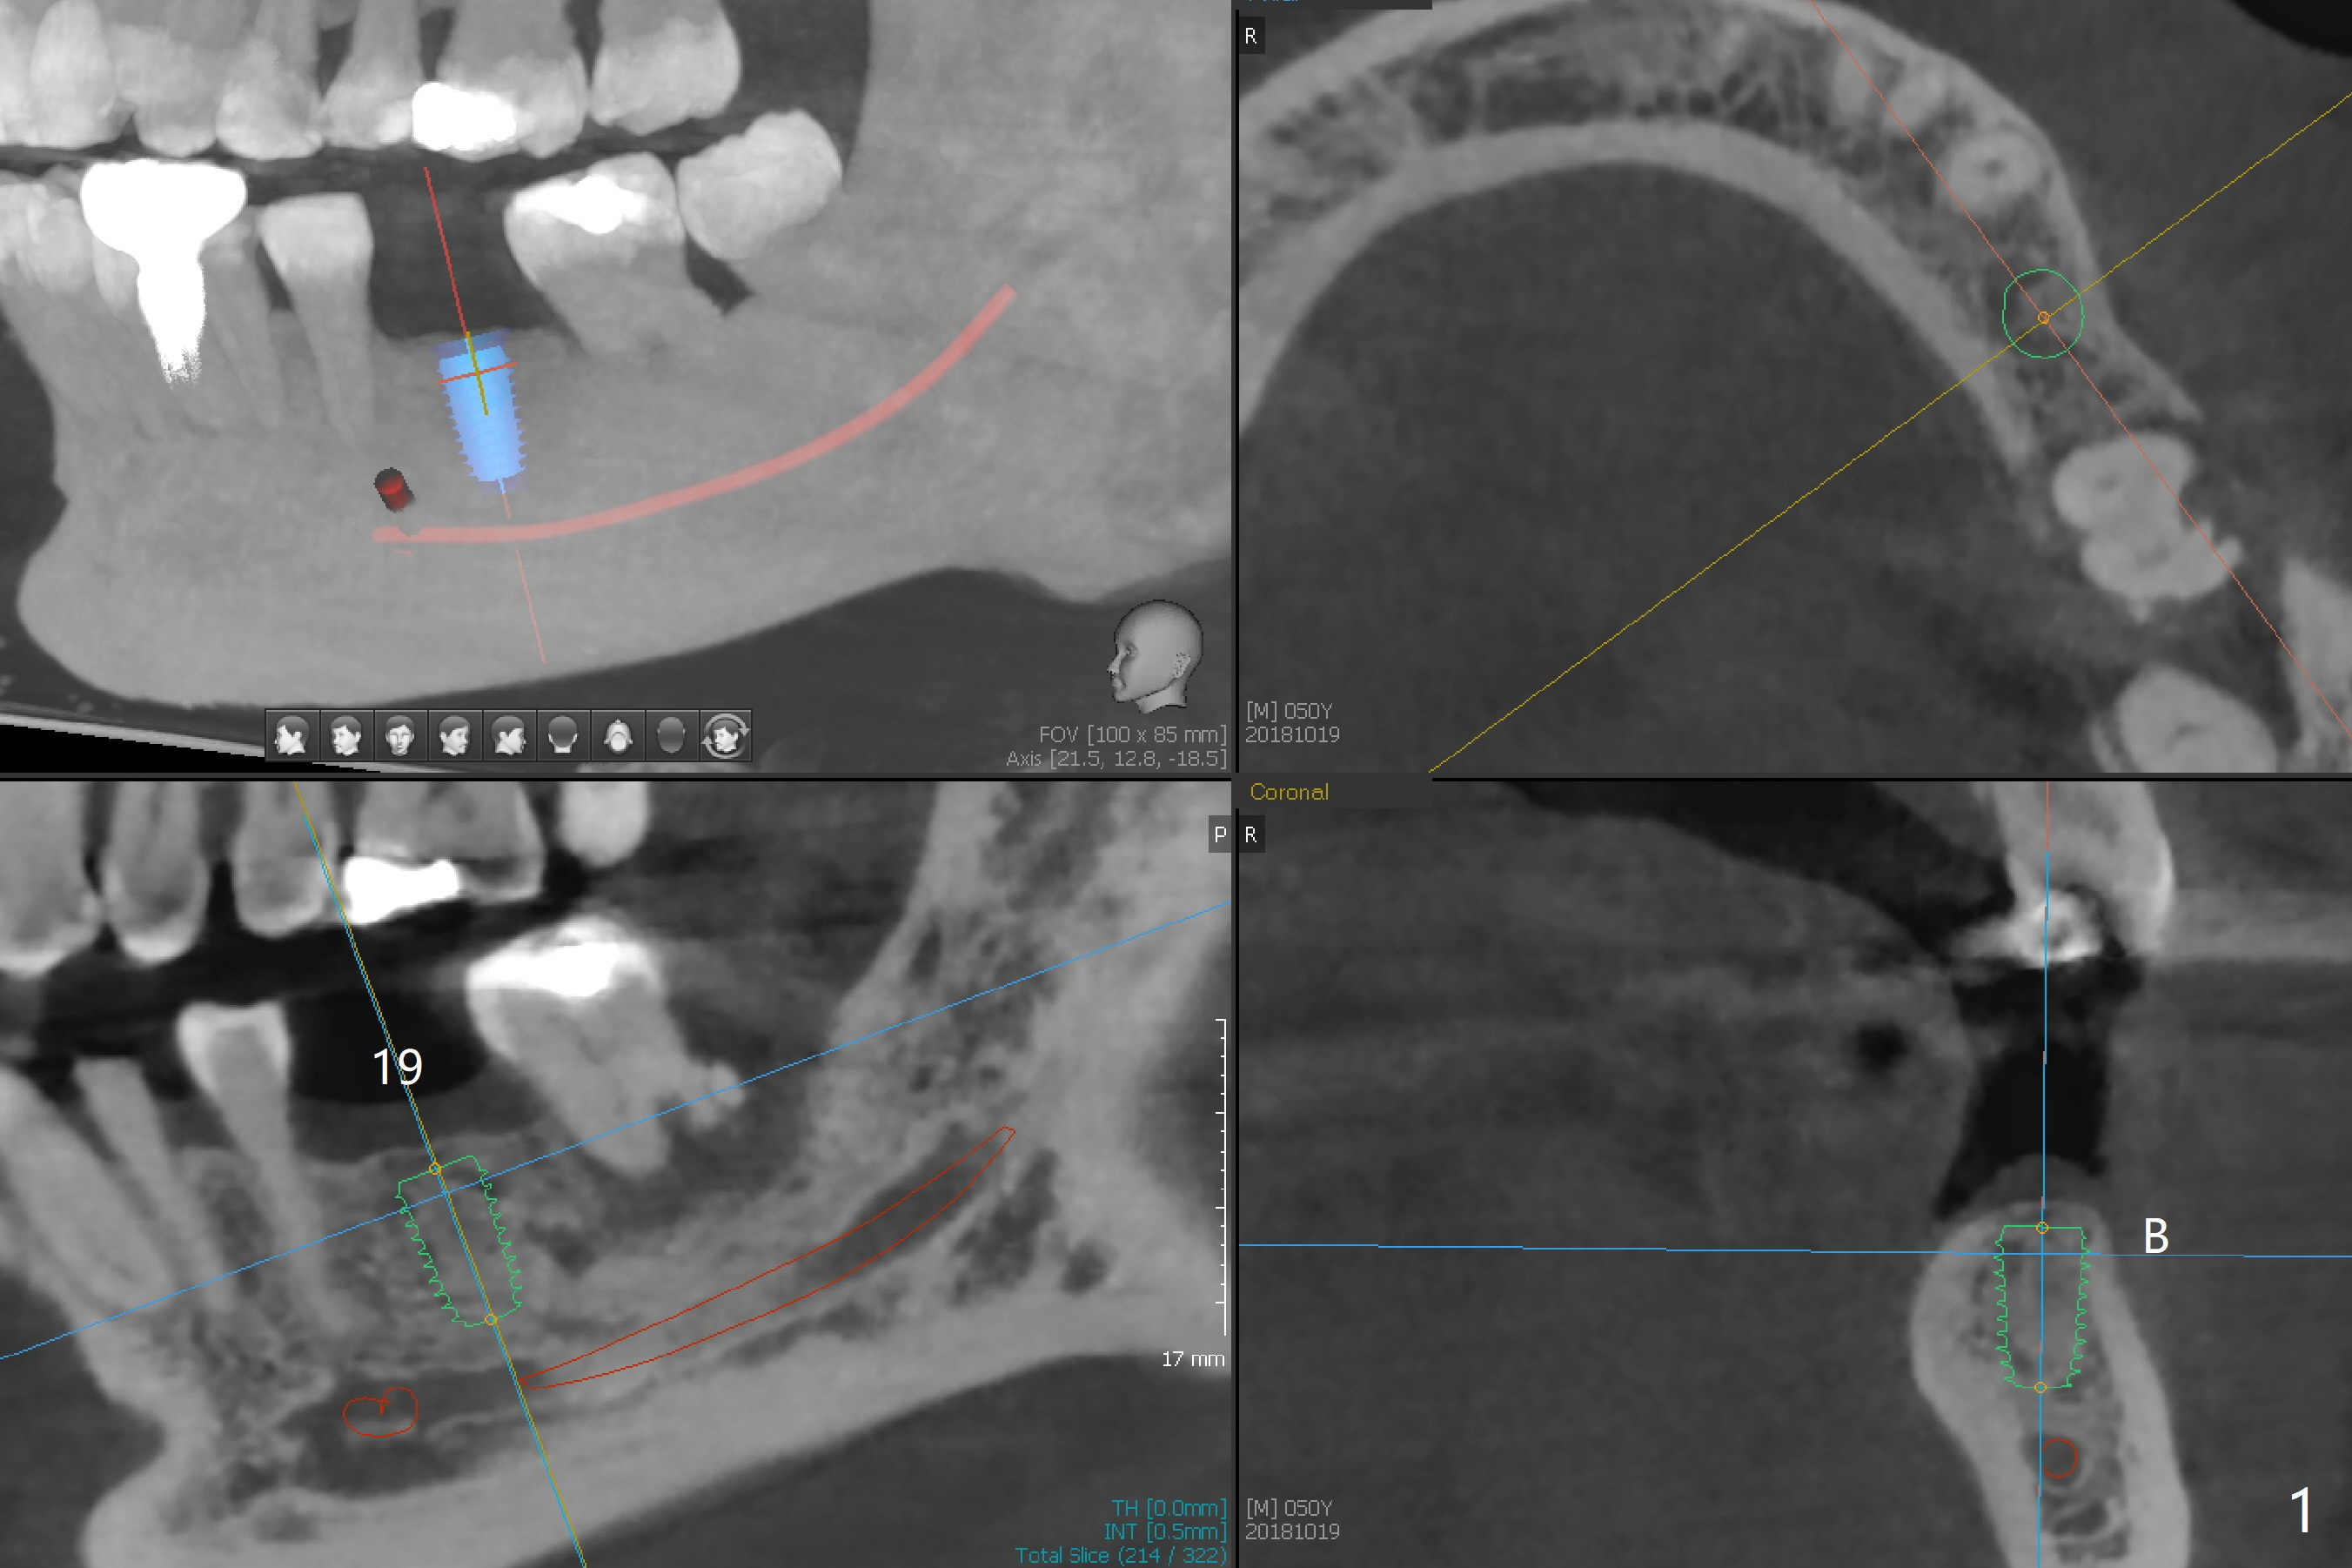

A 50-year-old man requests implant at #19 five months post cementation of crown at #30. Because of short bone, a 5x8.5 mm UF implant will be placed with guide (Fig.1).